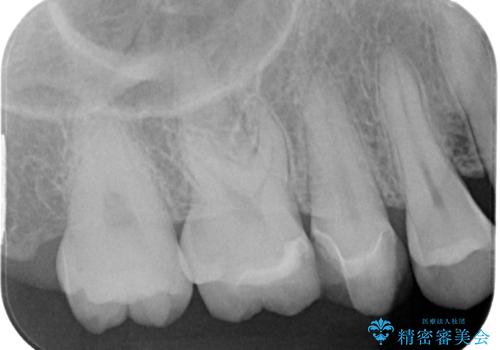

歯と歯茎の間に圧排糸と言われる糸を入れてシリコーン印象材にて精密な型どりをしました。

ハイブリッドインレーの装着時には、唾液の侵入を防ぐために、ラバーダム防湿を行いました。

見た目、機能面共に大変喜んでいただきました。